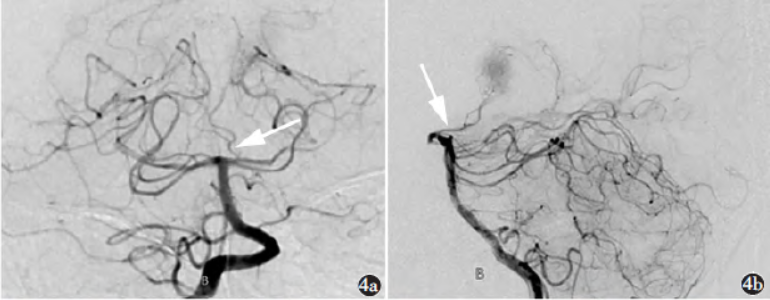

影像学检查:头颅MRI及MRA(图1~3)示双侧丘脑及左侧小脑半球多发斑片样T1WI低信号影、T2WI高信号影,T2WIFLAIR呈高信号,DWI信号随b值升高并增高,ADC呈低信号。DSA(图4)示Percheron动脉起源于左侧大脑后动脉P1段近段,右侧丘脑穿通动脉分支显影纤细,左侧丘脑穿通动脉分支血流缓慢。

图4a)DSA前后位示Percheron动脉起源于左侧大脑后动脉P1段近段(箭);b)DSA侧位示Percheron动脉(箭)

本例患者于超急性期脑梗死行头颅CT检查呈阴性,急性期及亚急性期头颅多次MR均提示双侧丘脑存在异常信号灶,以上均基本符合既往文献报道;其后,亚急性期行DSA检查,发现该患者双侧丘脑正中动脉存在IIb型变异,并提示该处动脉血流异常,但未有严重闭塞情况,考虑可能栓子较小或位于动脉远端,导致血流缓慢,造成急性缺血、缺氧并血管痉挛等情况,从而引起动脉支配区域的梗死。